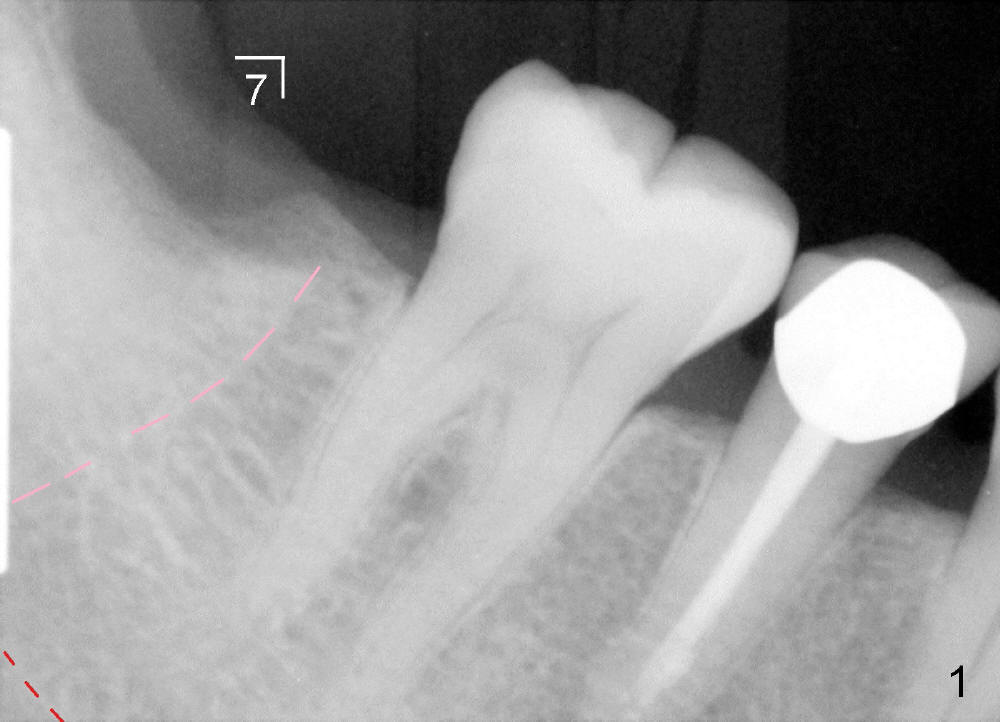

Maia (49 years old) is a typical gagger. She is apprehensive. Preop PA does not show the inferior alveolar nerve (IAN) canal completely (Fig.1 red dashed line). She is willing to get CT, which reveals the relationship between the healing socket and the nerve (N) (Fig.2 (sagittal section), 3 (coronal)). A 6x14 mm tissue-level implant is planned.

Infiltration anesthesia is administered with 68 mg of Septocaine, 34 mg of Lidocaine, 34 mcg of Epinephrine around the site of the lower right 2nd molar. An incision is made. A 2 mm pilot drill is used to initiate osteotomy at the depth of 8 mm. A parallel pin is inserted for the 1st intraop PA (Fig.4: P), which shows once more time the likelihood of incooperation from the patient. Combined with the information from CT, it appears alright to continue increasing osteotomy in the diameter and depth until 5x11 mm (Fig.5,6 (T: tap)). A 6x14 mm tap is inserted at 11 mm in bone. When the tap is removed, an explorer is used to check the intrigity of the osteotomy walls. No vibration is palpated linguoapically during drilling and inserting taps. There is no abnormal hemorrhage from the osteotomy. Finally 6x14 mm implant is placed as expected (Fig.7). The wound is healing 6 days postop (Fig.8).

Bone density immediately next to the implant increases while the mesial lamina dura is disappearing 2.5 months postop or 18 months postop (Fig.9, as compared to Fig.1,7).